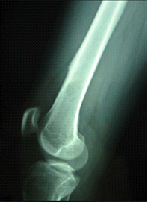

El osteosarcoma es el sarcoma óseo primario más común. La incidencia máxima está en la adolescencia, pero puede también ocurrir como malignidad secundaria en los adultos mayores. Los huesos largos que crecen rápidamente de la rodilla y del hombro son los más comúnmente afectados. El tratamiento siempre incluye la quimioterapia y la resección quirúrgica amplia

Osteosarcoma parostal Los osteosarcomas intramedulares clásicos constituyen el 75% de los osteosarcomas, mientras los tumores superficiales o yuxtaxorticales constituyen el 7% a 10%, entre los tumores superficiales, el subtipo más común es el osteosarcoma parostal, que está situado más comúnmente en la parte posterior del fémur distal y típicamente muestra un aspecto de pegado. Generalmente es una malignidad de bajo grado y por lo tanto se trata con la escisión local ampliada pero sin quimiotera